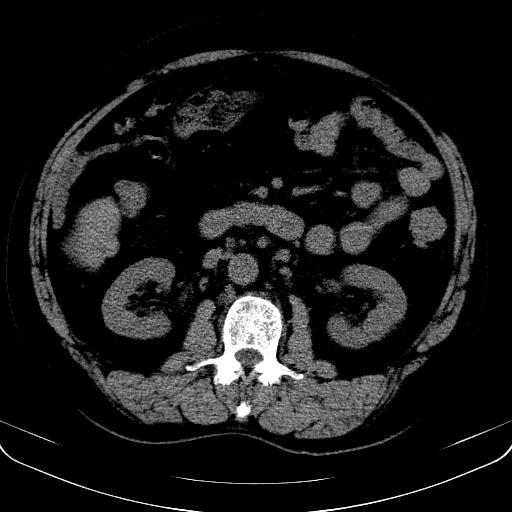

以下是引用jia119在2008-3-5 13:31:00的发言:[br]肝内多发片状低密度影,密度不均,我还是考虑肝ca可能,另肝内小囊肿,胆囊增大。

以下是引用随光逐影在2008-3-5 21:11:00的发言:[br]肝硬化伴门脉高压(食管下段静脉曲张),肝癌不排除。建议:行ct增强扫描检查。

以下是引用同在2008-3-5 13:56:00的发言:[br]考虑肝癌可能性大,胆囊增大.